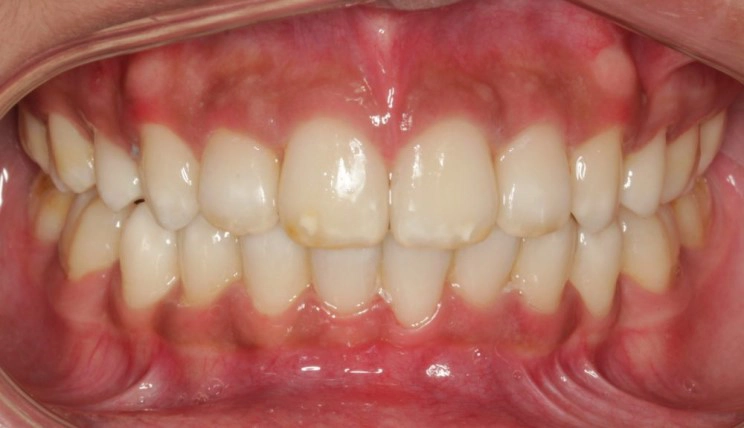

Crowding

Crowding is the condition in which there is a discrepancy between tooth size and space available for the teeth to be aligned in the dental arch

Patient Information:

Age: 17

Gender: female

Invisalign Treatment Option: Invisalign Comprehensive

Total Treatment Time:

29 months